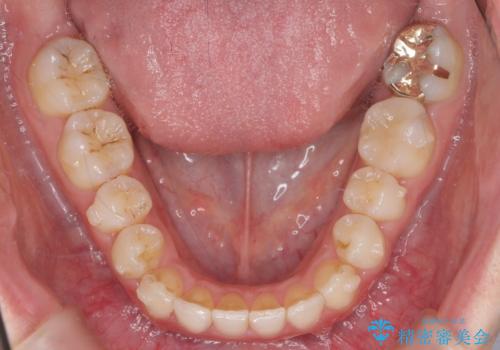

下の歯のがたつき 上より気になる

- 前歯のがたつきが気になって来院。

下の歯のがたつきが上よりも多い状態でした。

下の前歯は上の歯の内側にあるため、外に並べることができないため、上ほど簡単ではありません。

すき間をしっかりとって並べる必要があります。

今回は、下の歯を健康に支障が出ない範囲でわずかに削合し、並べるようにしました。(ディスキングといいます)

前歯のがたつきもしっかり治り、喜んでいただけました。

下の親知らずは虫歯になっていたため矯正前に抜歯しています。